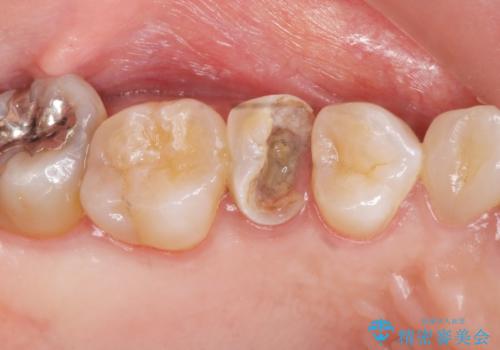

虫歯による歯の喪失 ジルコニアブリッジの製作

- 大きく歯が欠けてしまった虫歯の治療を希望され来院されました。

虫歯による歯の崩壊で歯を残すことが難しかったので抜歯を行い、インプラント・入れ歯ではなくブリッジによる咬合機能の回復を希望されました。